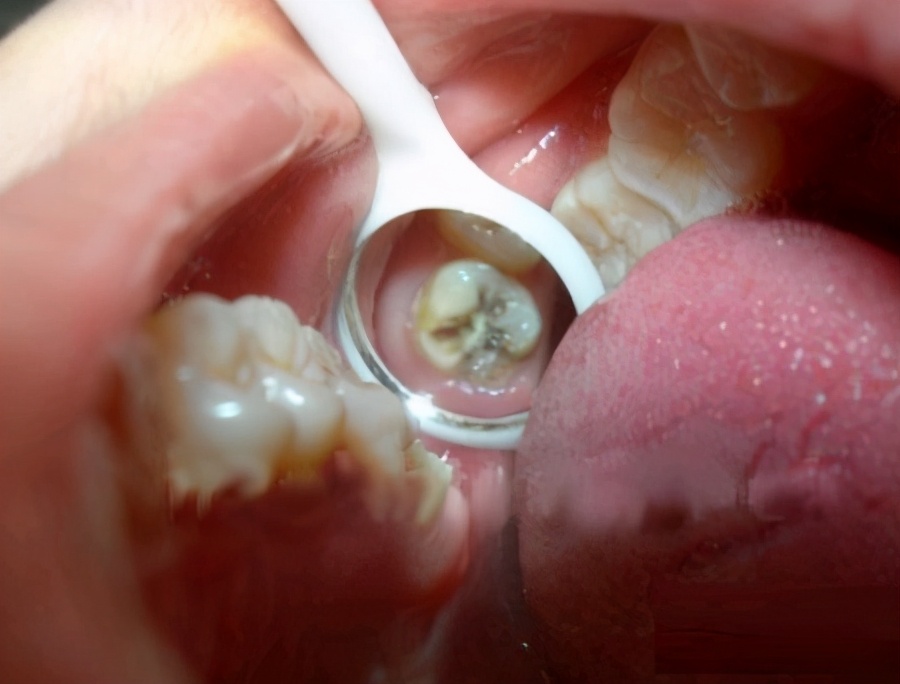

1.蛀牙引起的牙痛

这种情况在许多青少年中更为常见。它是一种细菌性疾病,可引发牙髓炎和根尖周炎。主要症状:开始时疼痛不明显,当牙齿受到一定程度的损坏时,会接近牙齿神经或到达牙齿神经时,它将使您疼得可以哭泣,难以忍受,而热,冷,酸痛会导致疼痛!您可以使用牙痛宁酊(ding),如果它不起作用并且无法忍受,这样的情况只能在消炎之后选择拔牙!